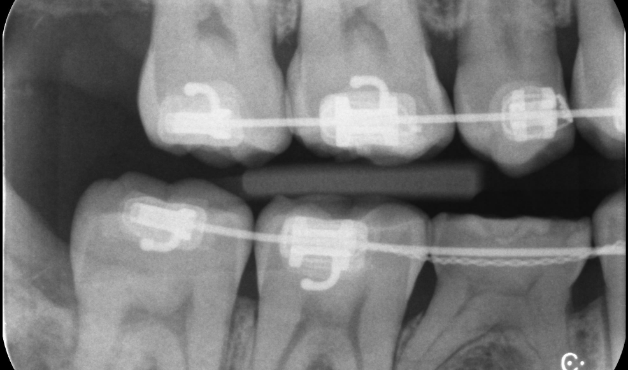

親知らずを活用し天然歯を保存した症例

タップで写真の拡大ができます。

Before

Under Treatment

After

主訴

インプラントはできないが、入れ歯もしたくない

治療内容

自家歯牙移植 / イニシャルトリートメント(大臼歯)レジンコア

治療期間

3ヶ月

治療費用

550,000

治療の

リスク

術後しばらくしてから骨性癒着、外部吸収を起こす可能性があります。